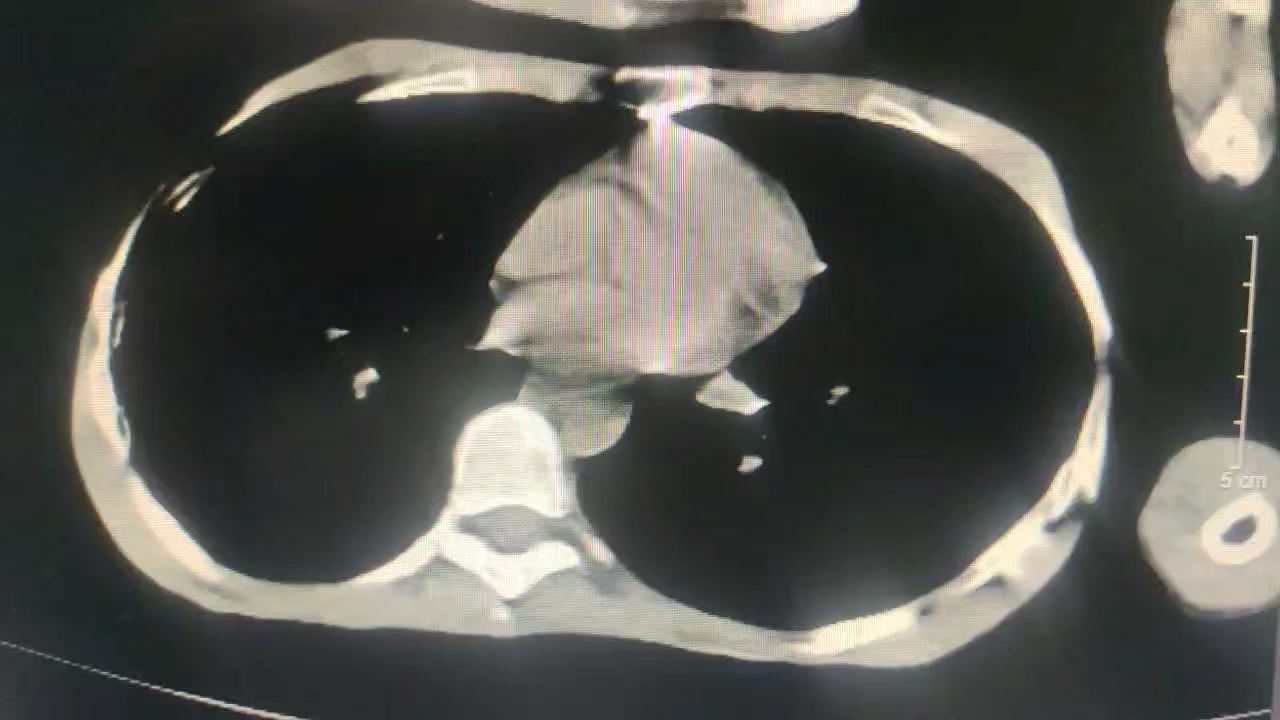

4、辅助检查:心电图:窦性心动过速。 血细胞分析:巴细胞计数 0.89 10^9/L 偏低, 淋巴细胞百分比 17.20 % 偏低, 单核细胞计数 0.69 10^9/L 偏高, 单核细胞百分比 13.40 % 偏高, 嗜酸性粒细胞计数 0.01 10^9/L 偏低, 嗜酸性粒细胞百分比 0.1 % 偏低, 超敏C反应蛋白(散射比浊法) 48.89 mg/L 偏高。生化全项:谷草转氨酶 57 U/L 偏高, *谷氨酰转肽酶 46 U/L 偏高, 前白蛋白 127.89 mg/dl 偏低, 间接胆红素 2.26 umol/L 偏低, *肌酸激酶 934 U/L 偏高, 肌酸激酶同工酶- 28.51 U/L 偏高, *乳酸脱氢酶 319.4 U/L 偏高, 羟丁酸脱氢酶 268.77 U/L 偏高, 肌酐(酶法) 110 umol/L 偏高, *尿素 8.9 mmol/L 偏高, β2-微球 5.73 mg/L 偏高, *葡萄糖 9.5 mmol/L 偏高, *钾 3.1 mmol/L 偏低, 铁 1.94 umoL/L 偏低。 颅脑+肺部CT:胼胝体未见明确显示,考虑先天缺如,请结合临床;双侧枕叶低密度影,建议进一步MRI检查;双肺多发磨玻璃斑片影,考虑炎症,建议临床治疗后复查。

入院第三天出现呼吸急促,血氧低,发热,呕吐:内科请会诊收入ICU,复查胸部CT,血生化:

考虑重症肺炎,予以无创呼吸机辅助呼吸,哌拉西林他唑巴坦+莫西沙星抗感染,胃肠减压,护胃,肠外营养等对症支持治疗,留取细菌培养。

血生化及炎症指标较前有所改善,复查CT:

最新CT提示肺部感染情况较前明显加重。